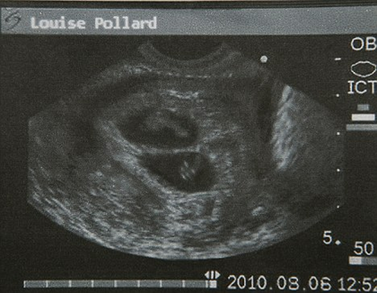

波拉德表示,她是本月6日在英國曼徹斯特一家私人診所做的超聲波檢查,影像資料顯示,她已經成功受孕8周而且懷的是雙胞胎。自今年6月上旬波拉德公開承認已答應為奧馬爾夫婦代孕以來,她一直是英國媒體關注的焦點之一。

2010年8月6日,超聲波檢查顯示波拉德懷的是雙胞胎。